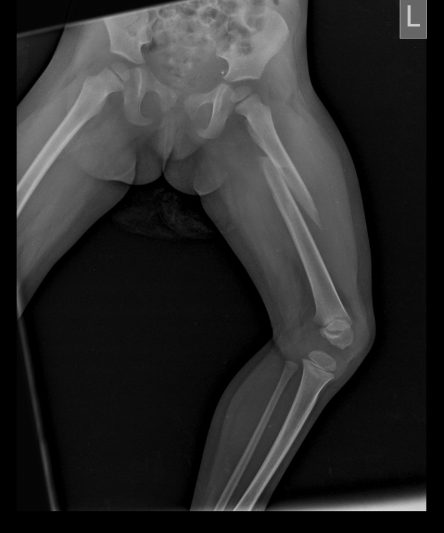

Microskan with Ultra high frequency can take the Lateral Lumbar Spine image of a 90 kg Patient with the correct image receptor